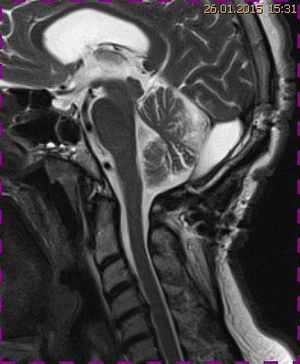

Abb. 1.2 Sagittales MRT (T2 TSE, 1 T): Streckfehlhaltung der HWS und oberen BWS, kein Frakturhinweis oder posttraumatische Myelopathie; die Kleinhirntonsillen reichen bis in das Foramen magnum

Abb. 2.1 Sagittales MRT (T2 TSE, 1,5 T): bei unveränderter Streckfehlhaltung der HWS 2 Monate nach der Erstuntersuchung Progredienz des Tonsillentiefstands, Syringomyelie

Das Fallbeispiel 1 zeigt im Verlauf eine Komplikation bei einer Arnold-Chiari-Malformation Typ 1 bei einem zum Zeitpunkt der Erstdiagnose 12-jährigen Jungen. Dieser hatte im Sportunterricht einen schweren Medizinball geköpft und ein Stauchungs-trauma der Halswirbelsäule erlitten. Nach anfänglich symptomatischer frustraner Therapie wurde er vom behandelnden Orthopäden zur MRT der HWS überwiesen. Es wurde eine Streckfehlhaltung und flachbogig rechtskonvexe Skoliose diagnostiziert, klinisch bestand ein Torticollis. Eine knöcherne oder ligamentäre Verletzung wie auch eine Schädigung des Rückenmarks bzw. eine intraspinale Bandscheibendislokation konnten bildmorphologisch ausgeschlossen werden.

Trotz weiterer Schmerz- und Physiotherapie konnte keine Beschwerdereduktion erreicht werden. 2 Monate später erfolgte eine MRT des Kopfes zum Ausschluss einer posttraumatischen Veränderung.

Bei dieser Untersuchung wurde übersehen, dass die Kleinhirntonsillen in das Foramen magnum disloziert waren und eine Arnold-Chiari-Malformation mit Erweiterung des 4. Ventrikels und des Aquäduktes inklusive Kleinhirntonsillentiefstand vorlag. Bei zwischenzeitlich auswärtig erfolgtem CT der HWS wurde eine Anlagestörung im kraniozervikalen Übergang beschrieben. Eine Kontrolluntersuchung des Kopfes weitere 4 Monate später dokumentierte neben einem medullären Ödem einen progredienten Tonsillentiefstand, der zur neurochirurgischen Behandlung mit operativer Erweiterung des Foramen magnum führte.